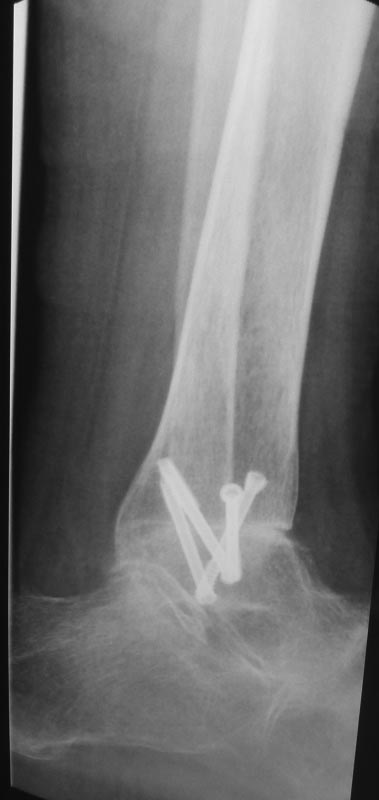

肖芯褌芯谐褉邪褎懈褟 褋褌芯褟 斜褘谢邪 锌褉懈褋谢邪薪邪 褔械褉械蟹 2 谐芯写邪 锌芯褋谢械 芯锌械褉邪褑懈泄. 袗 褔械褉械蟹  3

谐芯写邪, 锌褉芯褕械写褕懈屑 谢械褌芯屑, 锌邪褑懈械薪褌泻邪 褍锌邪谢邪 褋 谢械褋褌薪懈褑褘: 锌械褉懈锌褉芯褌械蟹薪褘泄 锌械褉械谢芯屑

斜械写褉邪. 效械褉械蟹 5 写薪械泄 锌褉懈械褏邪谢邪 芯锌械褉懈褉芯胁邪褌褜褋褟. 袨褌褋褞写邪 芯褌械泻 薪邪 褎芯褌芯 褋褌芯锌褘.

效褌芯 懈薪褌械褉械褋薪芯, 褔械褉械蟹 2 屑械褋. 锌芯褋谢械 芯褋褌械芯褋懈薪褌械蟹邪 锌邪褑懈械薪褌泻邪 薪邪锌懈褋邪谢邪, 褔褌芯

褌芯谢褜泻芯 褌械锌械褉褜, 锌芯褋谢械 锌械褉械谢芯屑邪, 褋屑芯谐谢邪 芯褖褍褌懈褌褜 芯锌芯褉褍 胁褋械泄 锌芯胁械褉褏薪芯褋褌褜褞

褋褌芯锌褘. 袛芯 褝褌芯谐芯 锌芯谢褜蟹芯胁邪谢邪褋褜 懈薪写懈胁懈写褍邪谢褜薪褘屑懈 褋褌械谢褜泻邪屑懈.